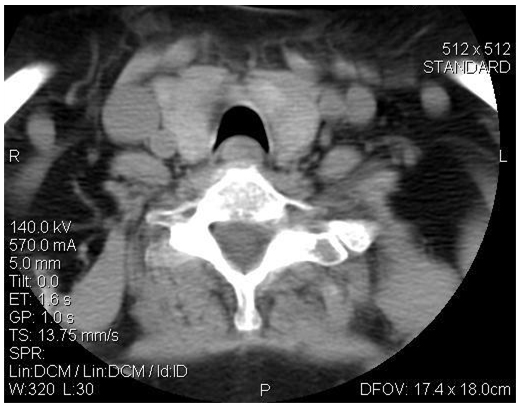

Figure 4. Pre-operative CT scan of the neck demonstrating crescent trachea sign